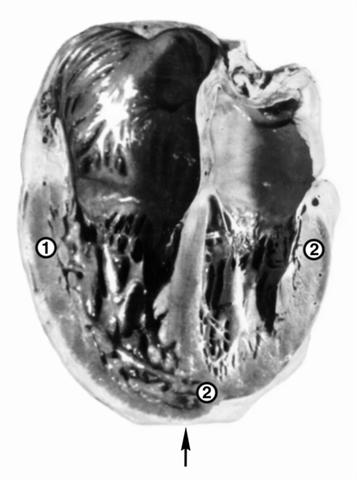

Рис. 1. Макропрепарат сердца при первичной легочной артериальной гипертензии: гипертрофия трабекул и стенки (1) правого желудочка, которая по толщине превышает стенку левого желудочка (2), расширение правых полостей сердца, верхушка сердца (указана стрелкой) сформирована правым желудочком.